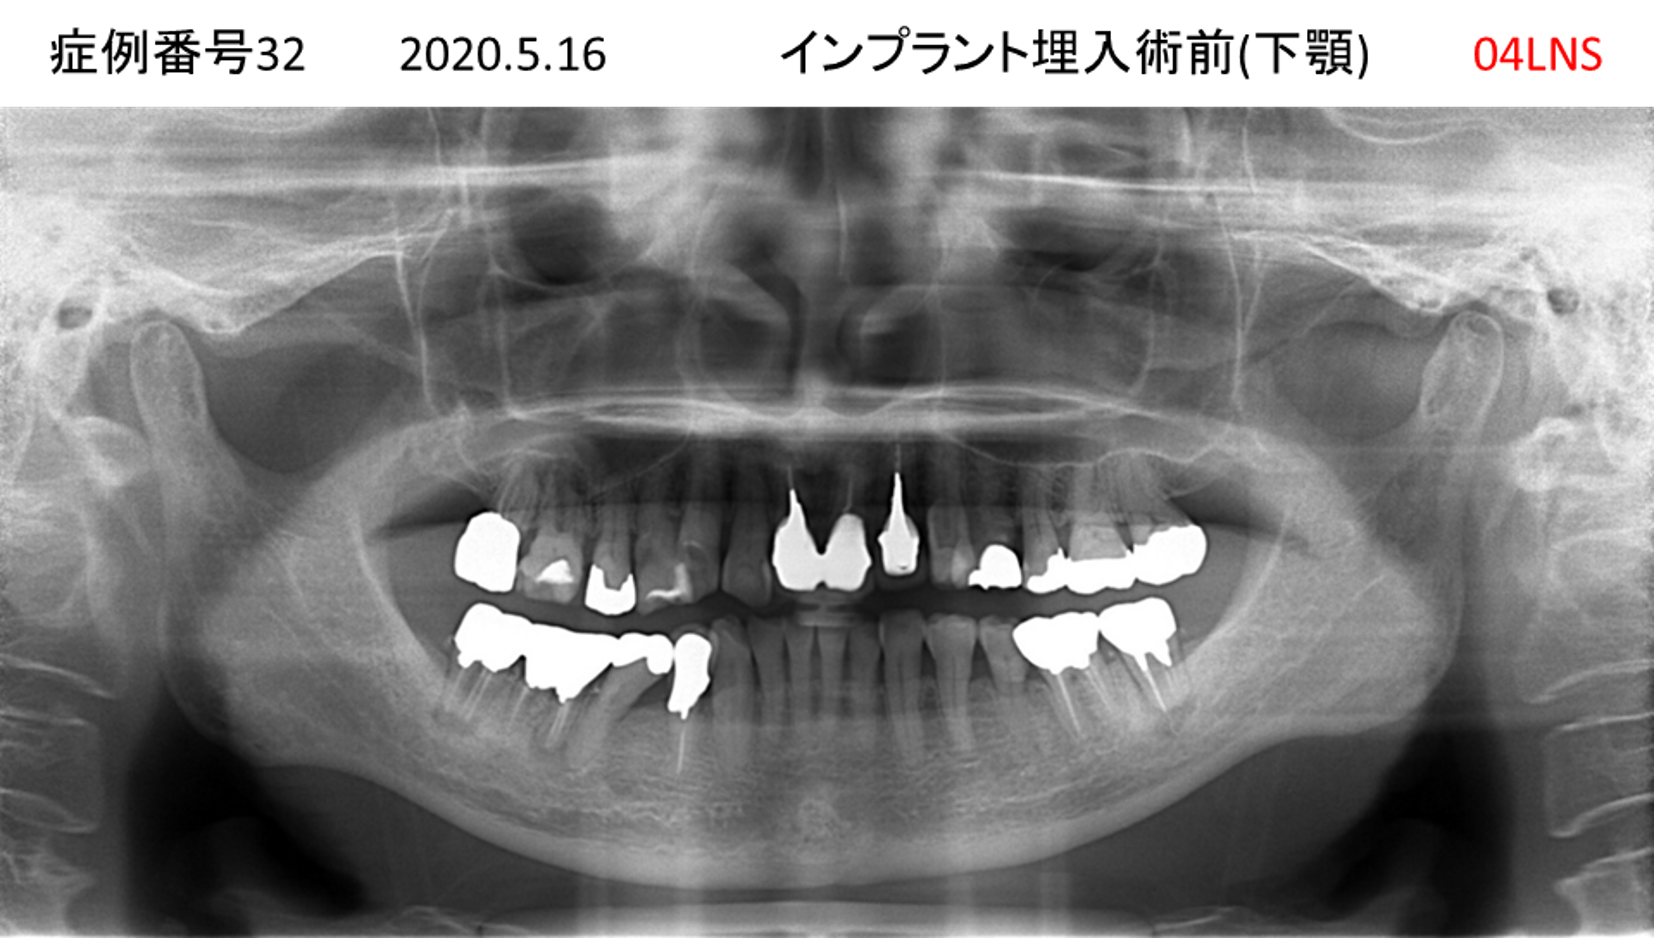

全く噛めない患者様のインプラント症例

| 治療名称 |

インプラントAGC |

| 治療費用 |

860万円+税 |

| 治療期間 |

12か月 |

| 患者さんの症状(主訴) |

全く噛めない、ごはんが後もに食べられるようになりたい、人前で口元を隠したくない |

| 治療内容 |

サイナスリフト、GBR、インプラント、AGC |

| 治療結果 |

しっかり噛めて踏ん張ることができる。食べ物をを選ばなくて済む、何でも食べられる、体重が増えた。見栄えがきれいすぎて自分じゃないみたい |

| 治療の注意点(リスク/副作用) |

インプラントが壊れたら再治療が必要 |